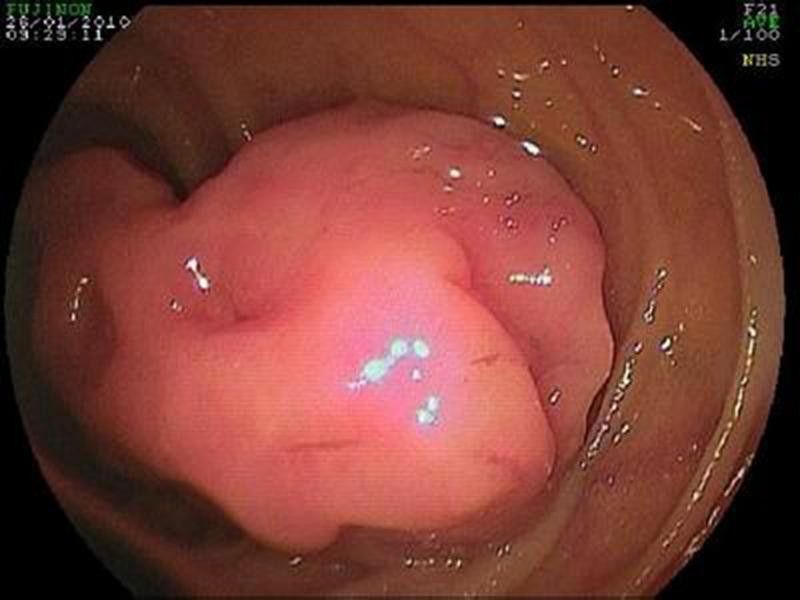

直腸腫瘤 良性